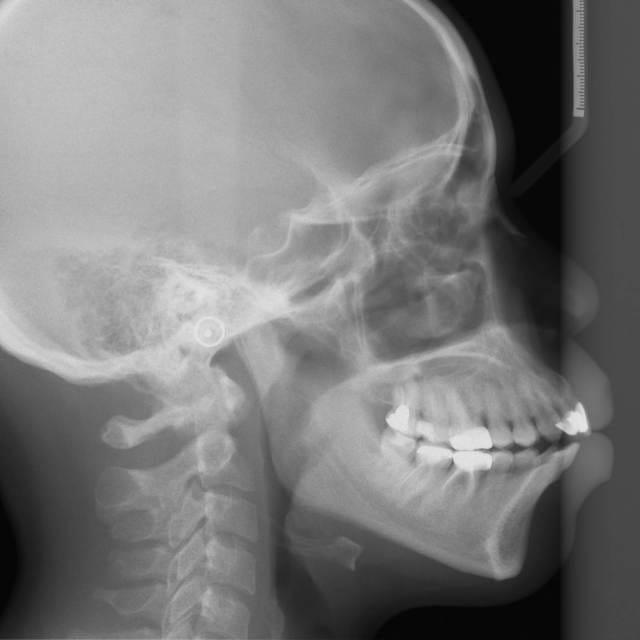

ATM: ouverture en baïonette, luxation réductible antéro médiane unilatérale, pas de douleur.

On est effectivement en cl II 1 dont l'overjet est masqué par d'un côté la béance et de l'autre par la version des incisives mand.

concernant la béance labiale, il n'y en a pas ,la photo de face est un sourire;

de plus, on voit que toute l'arcade est "gingivale" et comme tu dis, on va à l'encontre de la réduction de la béance en cas d'ingression des incisives donc on va penser à autre chose.

En quoi l'extraction des molaires facilite la rétraction par rapport à l'extraction des 4 voire au 5 ?

voici la pano

la lésion endo paro sur la 36 sera traitée dans un premier temps, soit par reprise d'endo + curetage paro soit par...extraction!